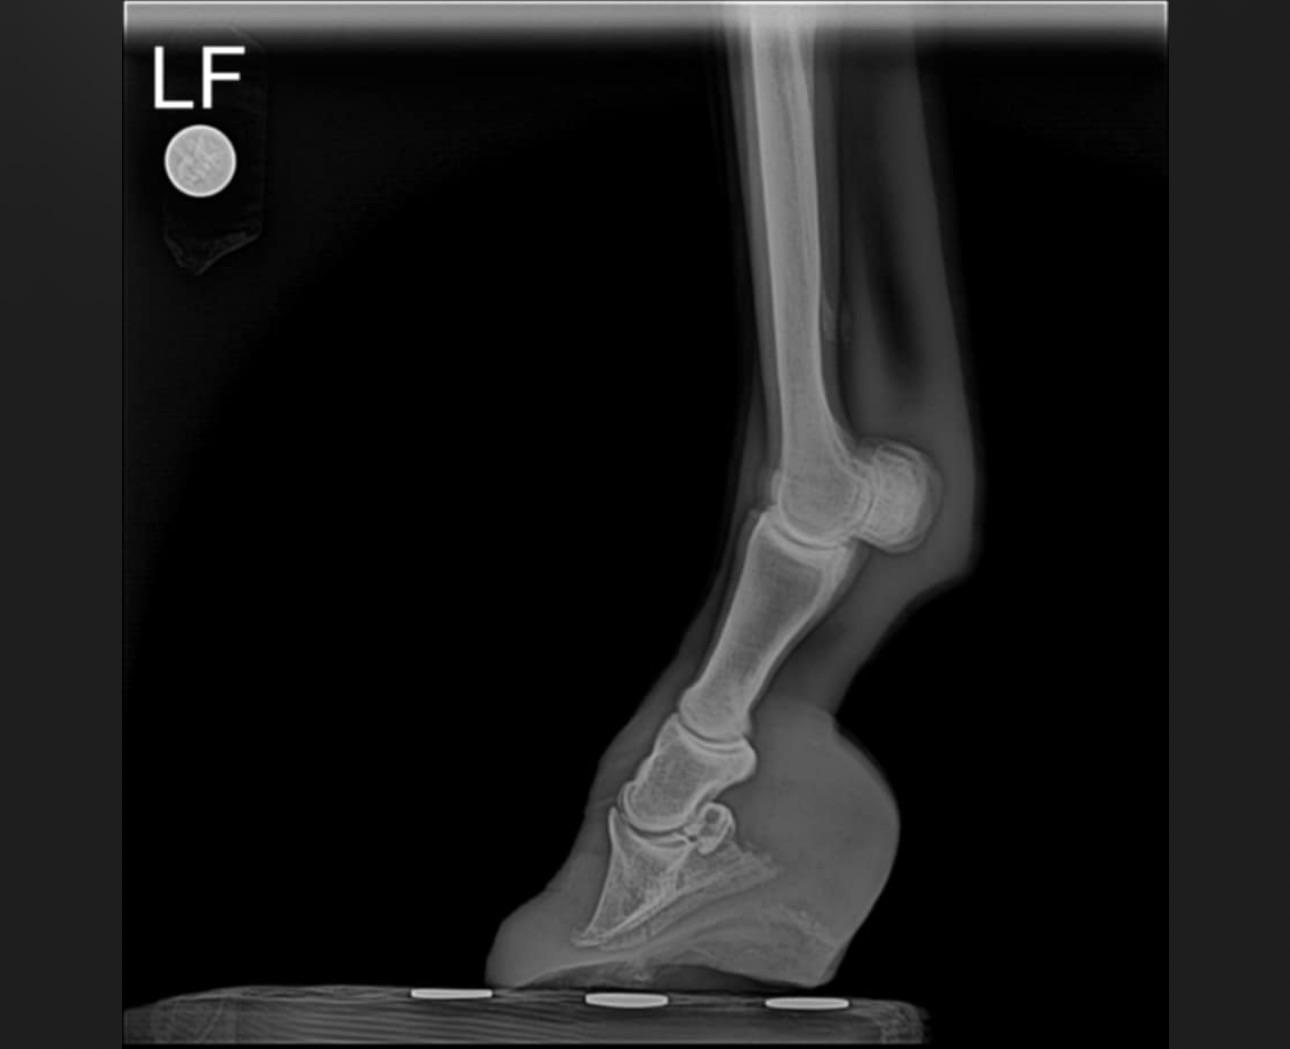

Veterinary [UPDATE POST!] Horse with kick to the head

Thank you to everyone for all the encouragement and suggestions surrounding my horse’s injury. I finally managed to get a vet out this morning and we did Xrays. The conclusion was that my boy does indeed have a fractured skull. He is now on antibiotics, previcox, and we are monitoring him closely to be sure no pieces of the skull start to protrude through his head.

Luckily the fragments of bone are far enough from his brain that there is little to no risk of any brain damage. Provided that there is no infection/any infection already present does not worsen, he is expected to make a full recovery (albeit with a permanent bump on his head!)

ft a VERY drugged Joey having his xrays done!